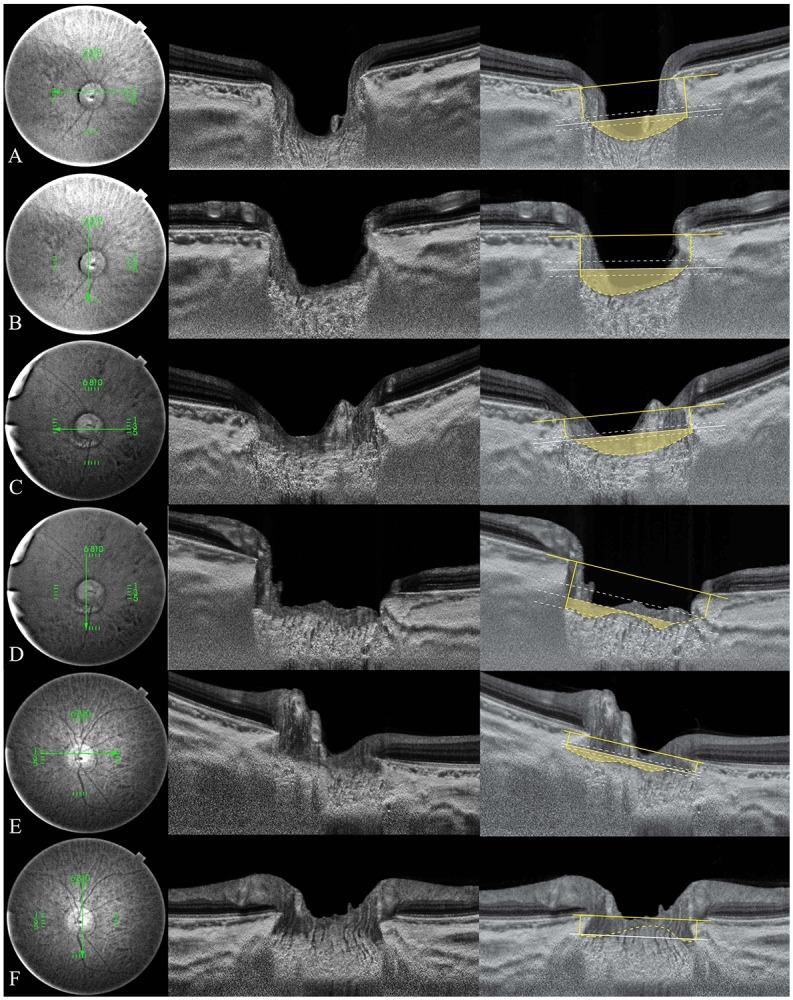

A total of 108 eyes with POAG and 61 healthy eyes were recruited. Based on the baseline IOP, the POAG eyes were divided into higher-baseline IOP (HTG; baseline IOP > 21 mmHg, n = 38 eyes) and lower-baseline IOP (NTG; baseline IOP ≤ 21 mmHg, n = 70 eyes). The anterior laminar insertion depth (ALID), mean LC depth (mLCD), and the LC curvature index (mLCD-ALID) were measured, and compared among the three groups. The regional variation of LC structure was evaluated by vertical-horizontal ALID difference.

The mLCD and LC curvature index were greatest in HTG eyes (520.3 ± 123.0 and 80.9 ± 30.7 μm), followed by NTG (463.2 ± 110.5 and 64.5 ± 30.7 μm) and healthy eyes (382.9 ± 107.6 and 47.6 ± 25.7 μm, all P < 0.001). However, there were no significant difference in ALID between HTG and NTG eyes. The vertical-horizontal ALID difference was larger in NTG eyes (72.8 ± 56.2 μm) than in HTG (32.7 ± 61.4 μm, P = 0.004) and healthy eyes (25.5 ± 34.8 μm, P < 0.001).